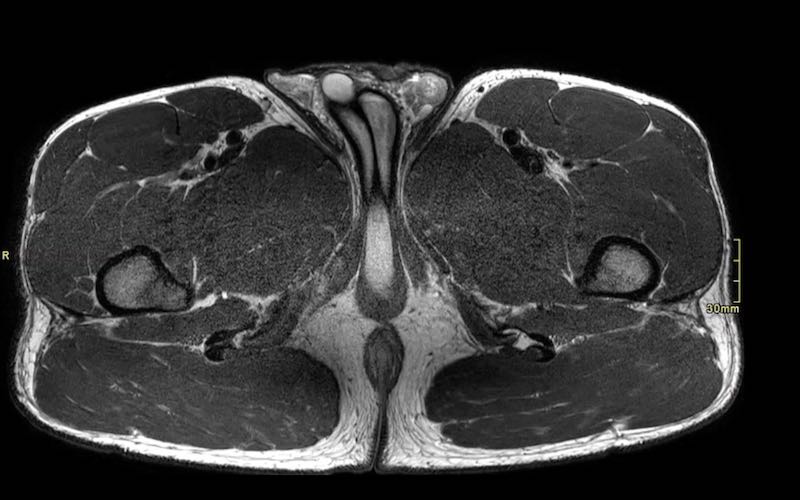

Mặt phẳng coronal so với mặt phẳng axial

Chỉ dựa vào các hình ảnh coronal đơn thuần, đôi khi khó có thể phân loại chính xác mức độ biến dạng. Cần sử dụng các hình ảnh axial để quan sát kỹ hơn.

Trên các hình ảnh axial này, có thể thấy tăng tín hiệu và dày lên của gân cơ nhị đầu đùi bên trái (vòng tròn chấm vàng) khi so sánh với bên không bị tổn thương (vòng tròn chấm trắng).

Tại đây bạn có thể cuộn qua các hình ảnh axial. Có thể phóng to hình ảnh bằng cách nhấp vào chúng.

Đây là tổn thương bán phần, bắt đầu từ gân chung ở phía gần, bao gồm cả vùng MTJ và gân trong cơ ở phía xa hơn. Chiều dài vùng phù nề và mức độ biến dạng gân đều ở mức độ cao. Trường hợp này được phân loại là tổn thương BAMIC 3b/c.